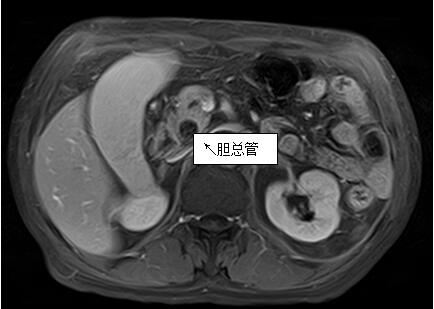

69歲王姓患者,因“發(fā)現(xiàn)無痛性黃疸1月”入院,根據(jù)患者病史,患者診斷傾向于壺腹部腫瘤所致梗阻性黃疸。予以完善腹部CT及上腹部MRI加MRCP均顯示肝內(nèi)外膽管擴(kuò)張,未發(fā)現(xiàn)明顯膽管,胰腺及十二指腸乳頭部腫瘤,且患者CA199正常。以前醫(yī)院未引進(jìn)超聲內(nèi)鏡,這類患者到此就遇到診斷瓶頸。此患者經(jīng)過消化內(nèi)科張丹霞副主任醫(yī)師完善超聲內(nèi)鏡檢查后,可以清楚顯示膽總管下段壁內(nèi)軟組織占位?;颊咄ㄟ^超聲內(nèi)鏡檢查診斷明確,轉(zhuǎn)至肝膽外科行手術(shù)治療。

上腹部MRI圖片